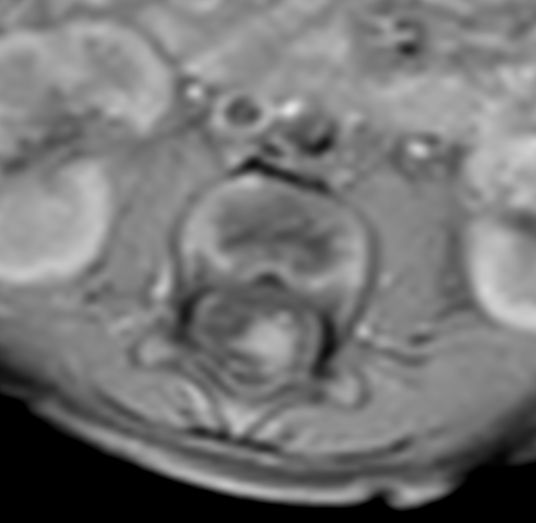

Pediatric Total Spine with spina bifida

Neonatal patient, 5 days old, with spina bifida